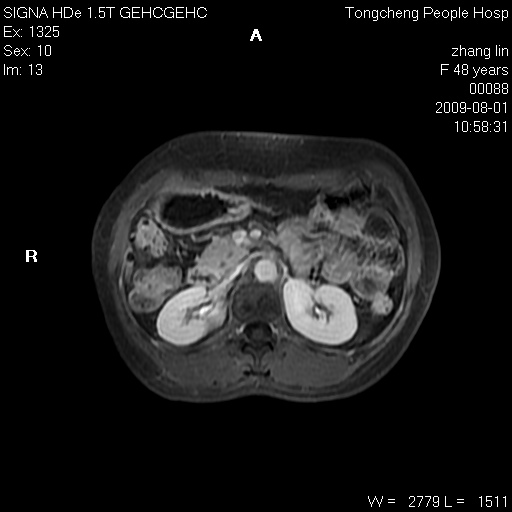

女,48岁。健康体检,彩超发现右肾占位性病变。平素健康。

临床诊断:右肾占位性病变,性质待定(囊肿?肿瘤?)。

上中腹部mr平扫+增强扫描,图像如下:

右肾上极见一类圆形病灶,t1wi呈等信号t2wi呈等高混杂信号,三期增强无强化,边界清---考虑囊肿出血。

同反相位均表现为等信号,病变无强化,考虑含蛋白的囊肿可能,弥散加权相或许有些帮助,